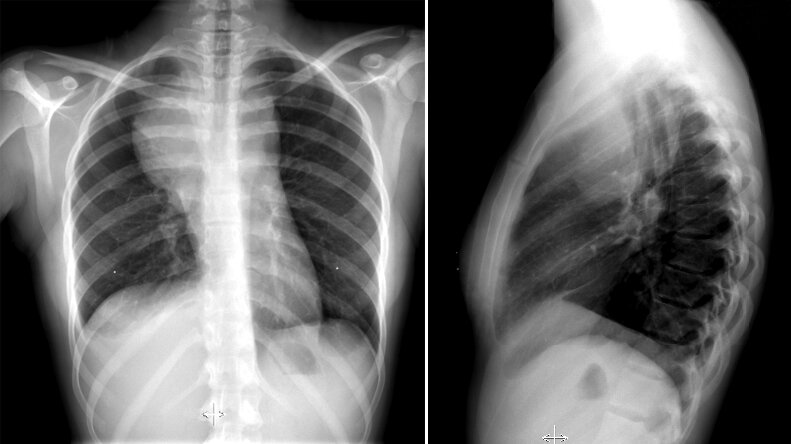

22-year-old woman is evaluated for fever, weight loss, and exertional dyspnea.

What is Hodgkin Lymphoma?